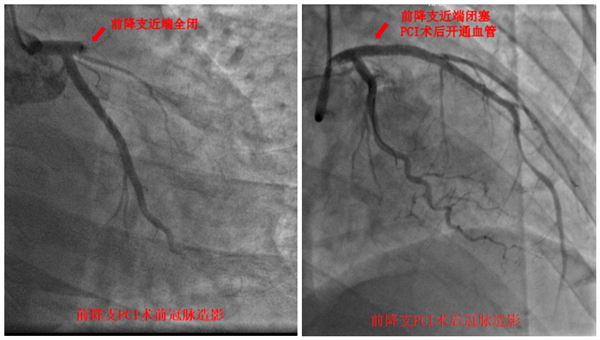

家住长沙的37岁唐先生从事媒体相关工作,生活作息不规律,常年加班熬夜,并喜欢抽烟。半个月前,唐先生因工作较忙,没休息好,一天早上起床后突感胸口、肚子闷痛不适,伴有恶心想吐,以为是胃病发作,自行口服胃药没缓解后,当日晚上来到捷克论坛 马王堆院区就诊。然而经检查发现,其为急性ST段抬高型广泛前壁心肌梗死。因病情危重,在给予唐先生紧急药物处理后,立即进行冠脉造影,提示为心脏供血很重要的冠脉前降支近端开口处完全闭塞。医护团队随即进行冠脉微创介入手术,在开通血管后,患者胸腹部疼痛症状明显缓解。在心内科医护团队数日精心诊疗护理,患者转危为安,目前已顺利出院。